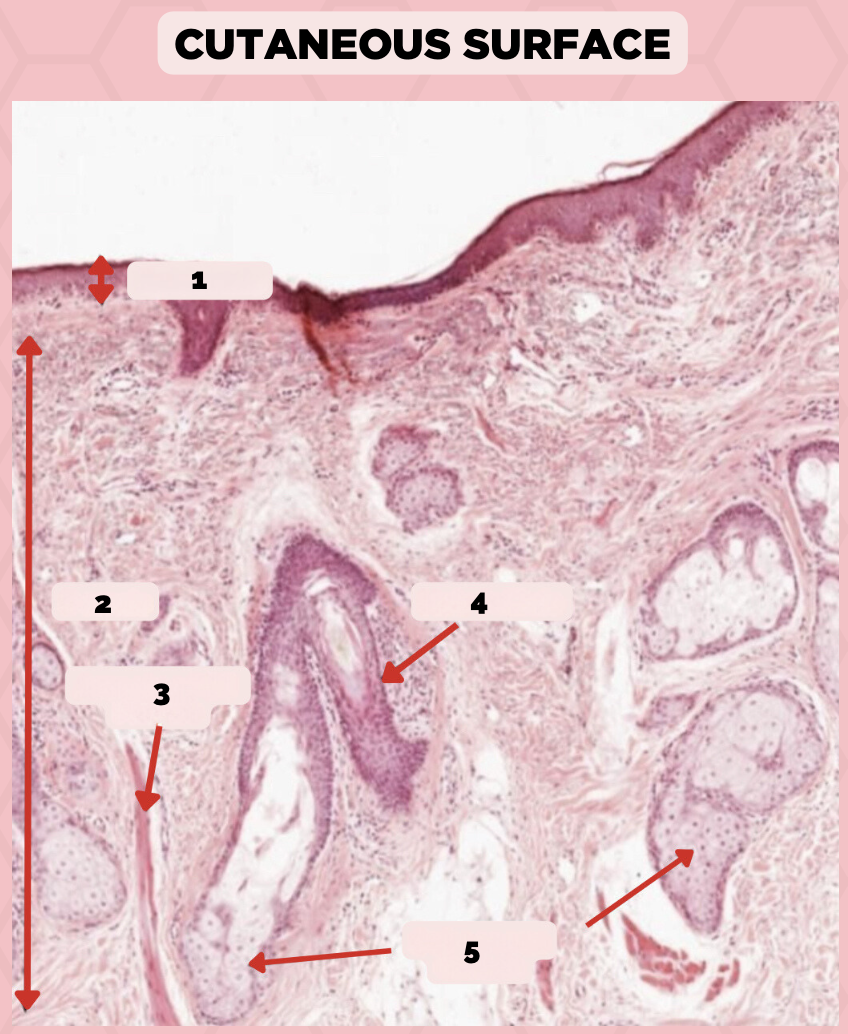

Lip

What is the specimen showed in the picture?

Epidermis

Identify the structure labeled as 1.

Dermis

Identify the structure labeled as 2.

Arrector Pilli Muscle

Identify the structure labeled as 3.

Hair Follicle

Identify the structure labeled as 4.

Sebaceous Glands

Identify the structure labeled as 5.